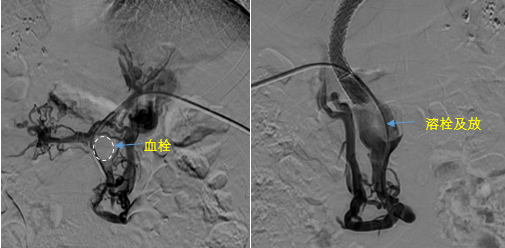

在西安國際醫(yī)學(xué)中心醫(yī)院,韓國宏教授對李女士進(jìn)行了細(xì)致的問診及檢查,在CT圖像上仔細(xì)的分析,針對患者特殊的病情制定了詳細(xì)的治療方案。第一次進(jìn)入手術(shù)室,在DSA的監(jiān)測下,造影過程中門靜脈血栓的輪廓逐漸顯現(xiàn)出來,見多識(shí)廣的醫(yī)生們也大吃一驚,發(fā)現(xiàn)遠(yuǎn)端脾靜脈及腸系膜上靜脈也存在大量血栓?;颊叩氖彻芪傅嘴o脈曲張非常嚴(yán)重,疏通堵塞的門靜脈已是刻不容緩。

見此情形,韓國宏教授憑借豐富的臨床經(jīng)驗(yàn)很快調(diào)整了策略,在超聲診療中心的協(xié)助下進(jìn)行門靜脈右支穿刺,并進(jìn)行造影,看到目標(biāo)血管后,韓國宏教授用“明修棧道,暗渡陳倉”的方法,讓來自脾臟和胃腸的血流終于暢通的回流到了肝靜脈。通過血流的沖刷以及抗凝溶栓藥物的作用,幾日后復(fù)查造影發(fā)現(xiàn)門靜脈血栓已逐漸變小,不會(huì)對回流到肝臟的血流產(chǎn)生大的阻礙作用,門靜脈的壓力顯著減小,患者再次出血的幾率也隨之降低。幾經(jīng)周折,這顆“定時(shí)炸彈”終于被拆除,李女士和她的家人多年來心里的石頭也終于落地。